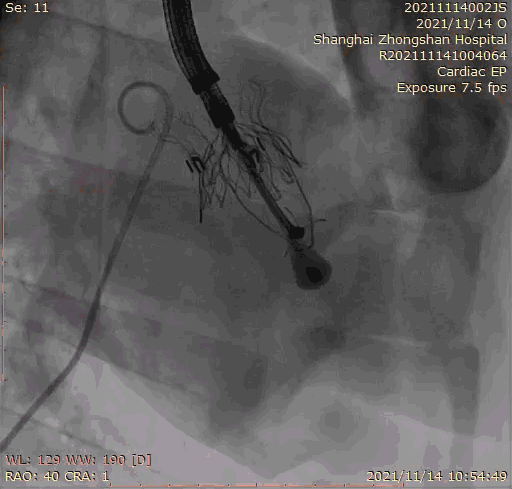

本次臨床前研究經(jīng)右側(cè)頸靜脈置入LuX-Valve Plus輸送系統(tǒng)可調(diào)彎鞘管,在DSA及超聲引導下將人工三尖瓣瓣膜植入到原有三尖瓣位置,利用獨特的錨定技術(shù)將人工瓣膜支架可靠固定在預(yù)定的位置。

上海中山醫(yī)院葛均波院士、錢菊英院長、周達新教授、潘文志教授、潘翠珍教授、李偉教授共同完成此次臨床前研究。術(shù)后葛均波院士對Lux-Valve Plus的器械操作性能給予了高度評價,DSA和超聲影像也顯示出在本次研究中Lux-Valve Plus的安全性和有效性俱佳。